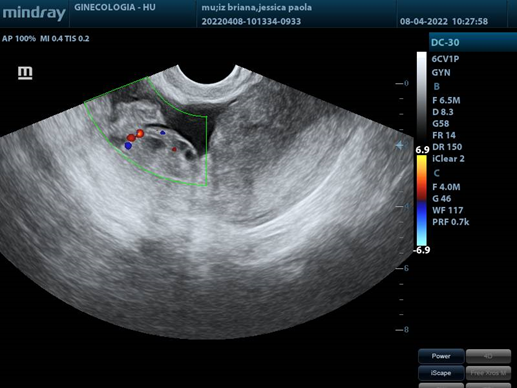

USG Transvaginal

1. Right adnexa, with heterogeneous image, hypoechoic mass, with clear border. with distance of 11.26X11X8.6cms.

1. Acoustic attenuation posterior a hypecoic mass en right adnexa.

1. Right adnexa with a deep flow of doppler color.